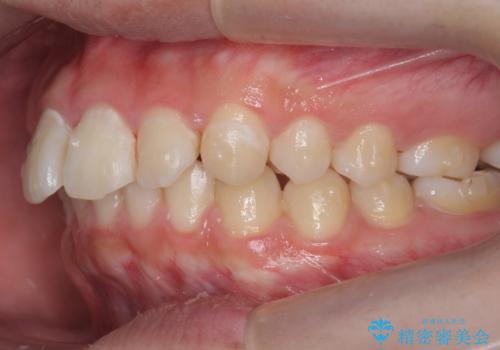

出っ歯が気になる 歯をぬかずに治療

- 前歯が出ているのを気にして来院。

左のかみ合わせが1本分ずれていましたが、機能的には問題ないのでそのまま変えずに治療しています。

ずれている分を、上の歯を1本抜くか(ワイヤー矯正になります)、右上の奥歯を1本分後ろに送るか、そのまま前歯を並べるのかを選んでいただきました。

右のかみ合わせをそのままに、最小限の動かし方で見た目を改善しました。